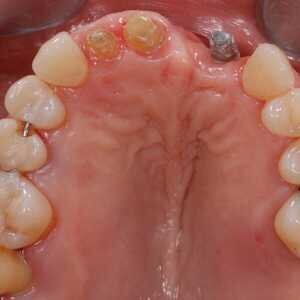

Dans cet article, nous présentons un cas clinique qui montre comment une mauvaise mise en place d'un implant peut rendre impossible la réhabilitation prothétique, ce qui nécessite une nouvelle planification chirurgicale et de réhabilitation pour obtenir l'esthétique souhaitée. Le patient se présente à notre observation avec une réhabilitation prothétique incongrue, avec bride en résine, support dentaire et implantaire, avec la présence d'un implant en position 2.1 vestibulaire et avec l'émergence dans le fornix, dans la mucosa alvéolaire. L'évaluation de la tomodensitométrie montre la position incorrecte de l'implant et la perte constante dans le sens transversal de la structure osseuse (Figs. 1, 2). Par conséquent, le plan de traitement suivant a été choisi : retrait de l'implant et préparation prothétique de l'élément 2.3, fabrication d'un premier support dentaire temporaire pour guider la cicatrisation des tissus (Figs. 3-7). Après 4 mois, une greffe d'épithélium conjonctif libre est réalisée avec ablation du palais pour compenser l'espace transversal des tissus mous, puis le provisoire est remodelé afin de faciliter la cicatrisation des tissus (Figures 8-11). Après 9 mois de maturation des tissus, la finalisation prothétique fixe avec support dentaire est réalisée (Figs. 12-14).